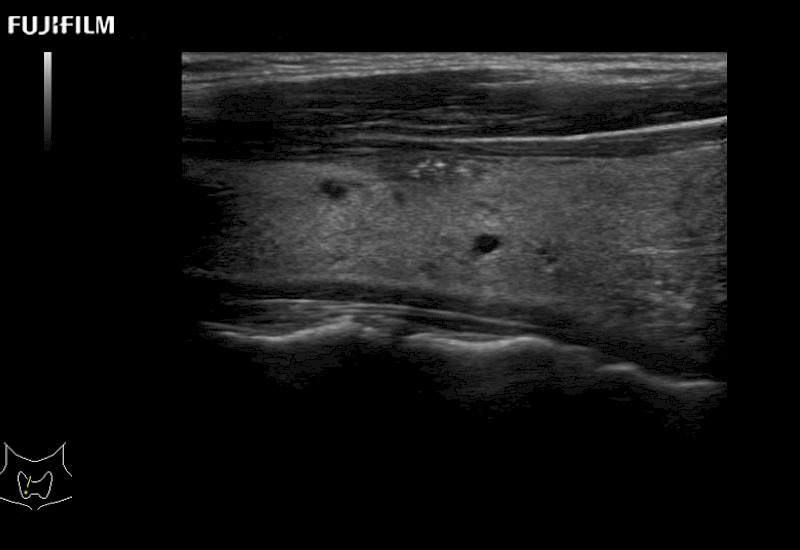

Our dedication to Surgical Oncology allows us to offer superior image quality, outstanding system reliability and intuitive use of cutting edge technology.

The ARIETTA 750 incorporates all of the proven technologies and functions that medical professionals have come to expect from Fujifilm Healthcare.

ARIETTA 750 is the definitive diagnostic ultrasound solution for any clinical setting - Private Office, Imaging Center, or Hospital. The ARIETTA platform provides the ultimate in clinical performance with its state-of-the-art features and large user-friendly display.

The ARIETTA 650 DI combines trusted Fujifilm Healthcare technologies and features tailored for surgical oncology.

Designed to meet the demands of surgeons, the ARIETTA 650 DI offers precise guidance. Its advanced capabilities and large, intuitive display offer accurate and efficient care in operating rooms and specialized surgical settings.